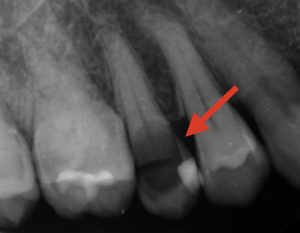

治療前

赤い矢印部分、黒くなっているところが虫歯です。虫歯が神経まで感染していたため、神経を取る処置「抜髄」を行いました。当院では根管治療を行う際には必ずマイクロスコープとラバーダムを使用します。マイクロスコープ・ラバーダムを使用した精密根管治療について詳しくはこちらをご覧ください。